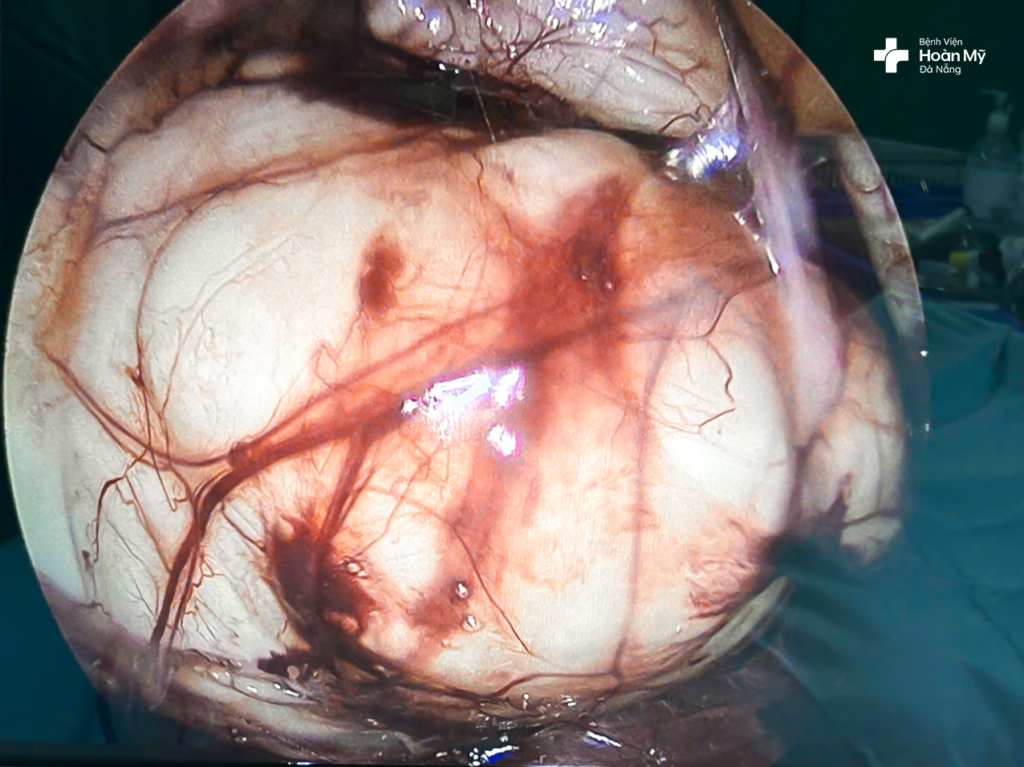

(hình 1) Hình ảnh chụp CT cho thấy khối u nang lớn chèn ép nội tạng

Xác định phải phẫu thuật, người bệnh tìm đến Bệnh viện Hoàn Mỹ Đà Nẵng. Tại đây người bệnh được thăm khám lâm sàng và cận lâm sàng để đánh giá lại thêm 1 lần nữa. Mặc dù đây là khối u có kích thước lớn nhưng các xét nghiệm máu và chẩn đoán hình ảnh hướng tới một khối u nang sau phúc mạc lành tính (hình ảnh CT Scan cho thấy một khối dạng nang 150 x 180 mm, ranh giới rõ, đè đẩy các tổ chức xung quanh, dịch đồng nhất và không ngấm thuốc cản quang), thể trạng người bệnh tốt, vì vậy các bác sĩ chỉ định phương pháp phẫu thuật nội soi sau phúc mạc bóc toàn bộ khối u làm giải phẫu bệnh lý.